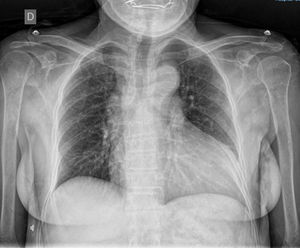

Case reportA 72-year-old female with hypertension. At the age of 69, she was diagnosed with mild aortic regurgitation, NYHA functional class I, and due to the COVID-19 pandemic, she lost follow-up. For the past eight months, she has reported a deterioration to NYHA class III, accompanied by chest pain, palpitations, and syncope. Physical examination revealed Müller's sign and a grade IV/VI holosystolic murmur at the aortic focus. The electrocardiogram showed sinus rhythm with criteria for left ventricular hypertrophy. The posteroanterior chest X-ray revealed widened hila, grade III cardiomegaly, and a prominent aortic knob (Fig. 1).